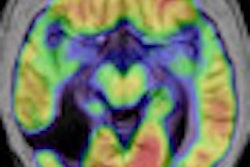

Scientists from the Medical Research Council's cognition and brain sciences unit used functional magnetic resonance imaging (fMRI) to watch and compare what goes on in the brains of normal people when they hear ordinary sentences and funny jokes, including puns.

By scanning the brains of 12 healthy volunteers, they found that the reward areas in the brain light up to a much greater degree when processing jokes than when processing normal speech. In the study, this reward response increased in line with how funny the participants found each of the jokes.